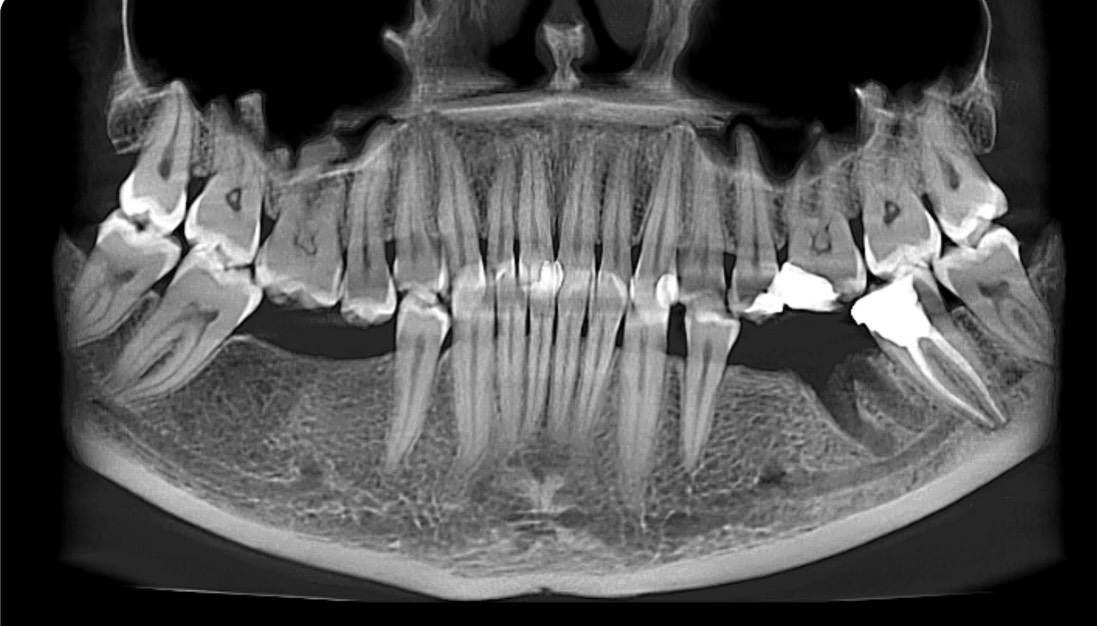

Мария2010 Опубликовано 7 часов назад Поделиться Опубликовано 7 часов назад Здравствуйте,подскажите пожалуйста ,по снимку видно ли,что в нижних семерках и восьмерках есть кариес? Ссылка на комментарий